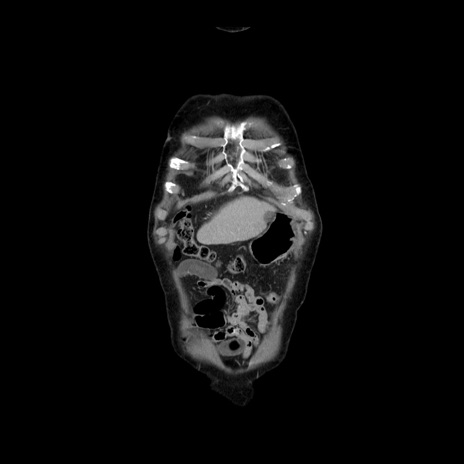

症例21(冠状断像)

【症例】70歳代男性

【主訴】腹痛

【現病歴】肝硬変・肝細胞癌にてかかりつけの方。約9時間前に食後より腹痛出現。症状が徐々に増悪し、嘔吐出現したため来院。

【既往歴】肝硬変、肝細胞癌(RFA、TACE後)

【身体所見】意識清明、表情苦悶様、BT 36℃、BP 129/78mmHg、P 88bpm、SpO2 97%(RA)、右上腹部から心窩部にかけて圧痛あり、反跳痛なし、筋性防御あり。

【データ】WBC 5800、CRP 0.16